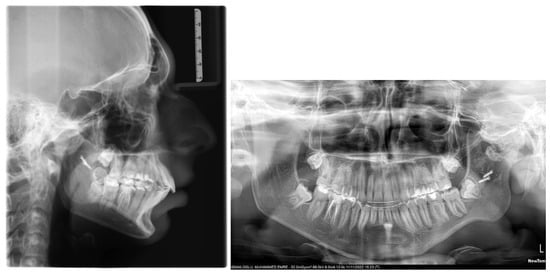

Significant improvements were seen in the post-treatment lateral cephalometrics (Figure 5), particularly the Wits and Pogonion to McNamara Nasion Perpendicular (Table 1). The mandible was advanced whilst the maxilla was restrained, as shown in the superimposition of pre-treatment and post-treatment lateral cephalograms (Figure 6). Even though the skeletal Class II jaw base relationship remained, the lateral cephalometric analysis revealed a decrease in the ANB angle (8.8°). The maxillary incisors were retroclined from 121.9° to 114.5° (Table 1). The post treatment panoramic radiograph showed good root parallelism without any visible signs of root resorption (Figure 5).

Figure 5.

Post-treatment lateral cephalogram and panoramic radiograph.